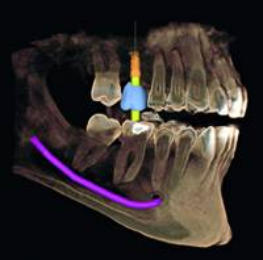

Anwendungsgebiete für die 3D-Diagnostik in unserer

Zahnarztpraxis Celle sind:

Implantologie Endodontie spezielle Parodontologie Chirurgie Zahnersatz Kieferorthopädie